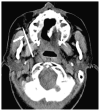

Cross-sectional imaging plays an important role in the evaluation of the retropharyngeal space (RPS) and the prevertebral space (PVS). Because of their deep location within the neck, lesions arising within these spaces are difficult, if not impossible, to evaluate on clinical examination. This article details the cross-sectional anatomy and imaging appearances of primary and secondary diseases involving the RPS and PVS, including metastasis and spread from adjacent spaces. The role of image-guided biopsy is also discussed.